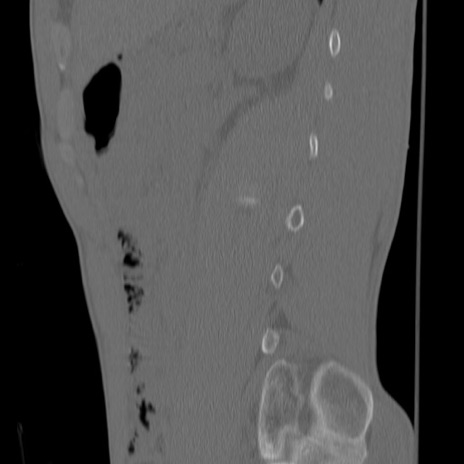

症例3 腰椎CT(矢状断像)

腰椎CT

冠状断像